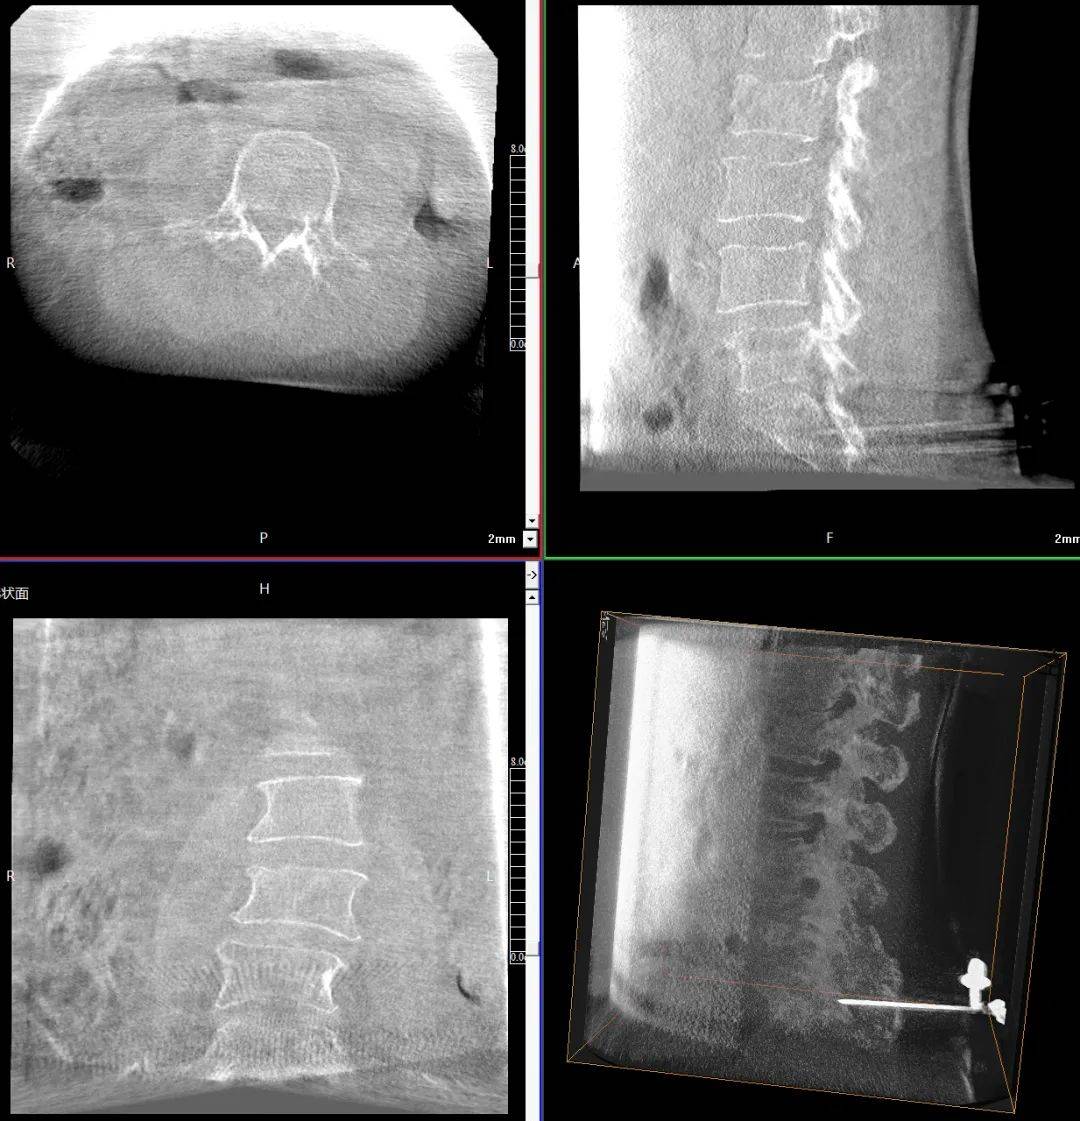

臨床表現(xiàn):患者主訴腰背部劇烈疼痛,活動受限;查體證實腰背部局部壓痛、叩擊痛明顯,尤其在受累椎體區(qū)域;影像學檢查顯示多節(jié)段椎體壓縮性骨折,椎體高度明顯降低,椎體形態(tài)不規(guī)則,椎體扭曲畸形,椎弓根狹窄。

患者術前影像